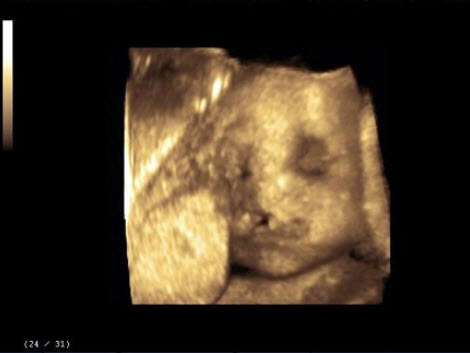

女性,25岁,停经35周。产前超声检查,图像显示的是胎儿的()

A.脊柱

B.四肢

C.颜面部

D.胸腔

E.腹腔